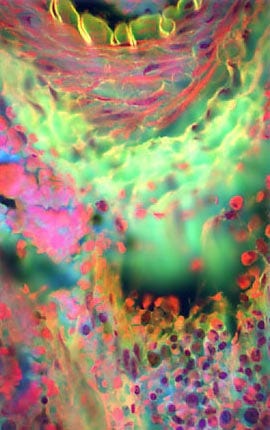

Mammalian Compact Bones

There are two basic structural types of bone in mammals, compact and spongy. Compact bone is very dense and hard on the outside, and makes up most of the bones in the arms and legs. The structural units are osteons, which are elongated cylinders acting as weight-bearing pillars that can withstand high levels of mechanical stress.